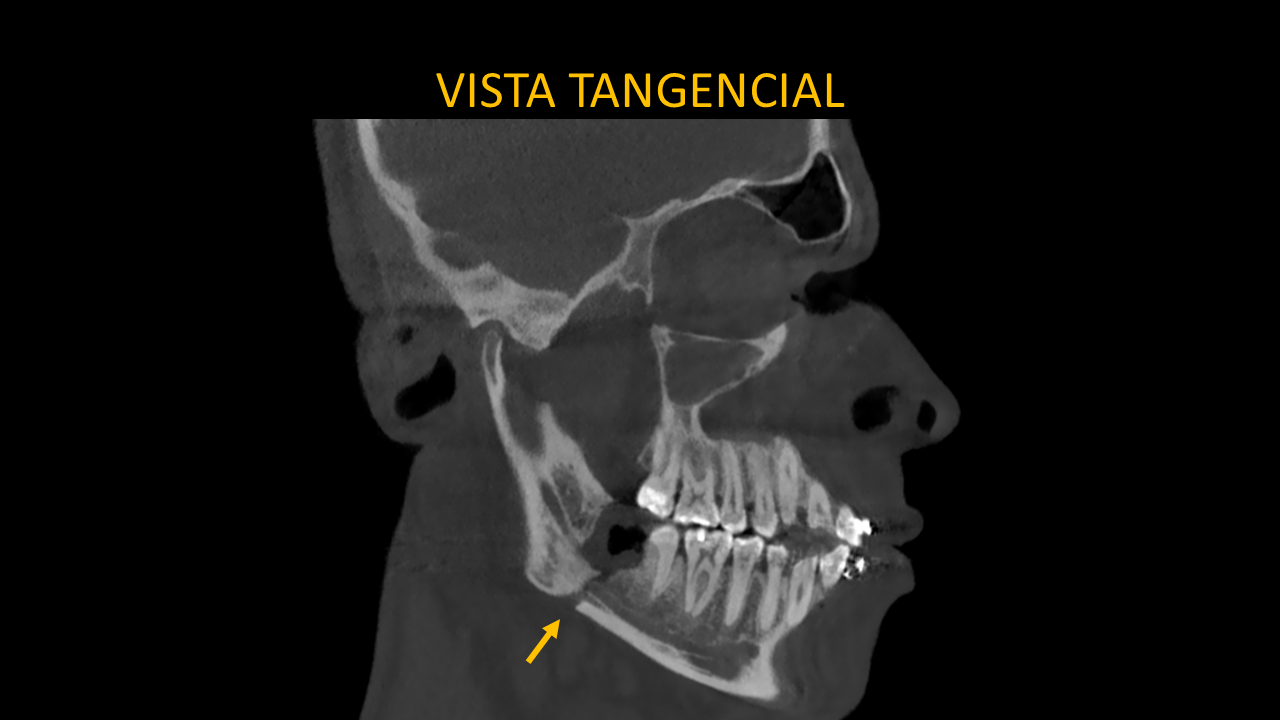

Figura 4: Vista Tangencial

En la vista tangencial (Figura 4) podemos apreciar que la línea de fractura se extiende desde el reborde alveolar en zona de pieza 48 hasta la basal mandibular de la escotadura antegonial derecha, también se evidencia la interrupción de la trayectoria del conducto dentario inferior.